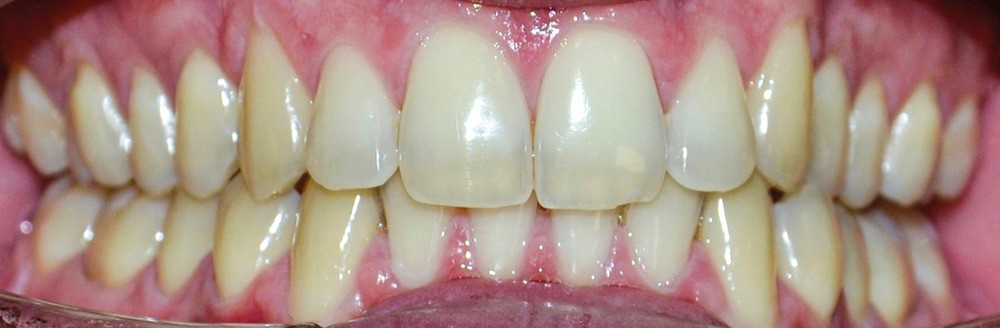

► L’entretien semi-directif met en évidence des signes d’apparition récente (un an environ), une aggravation progressive des symptômes, et la perception rapportée par le patient de moindres contacts occlusaux du côté gauche. L’examen clinique extra-oral révèle des douleurs musculaires lors de la palpation des muscles masséters, temporaux et ptérygoïdien médial gauche ainsi que des muscles sterno-cléïdo-occipito-mastoïdiens droit et gauche. Il n’y a pas de limitations d’ouverture buccale. L’examen clinique intra-oral révèle la présence d’une inocclusion dentaire gauche, qui s’étend des dents 23 à 27 (fig. 1 et 2). Il est à noter que la reprise de l’entretien ne rapporte pas d’antécédent de soins dentaires, orthodontiques et/ou prothétiques susceptibles d’engendrer une modification de l’occlusion.